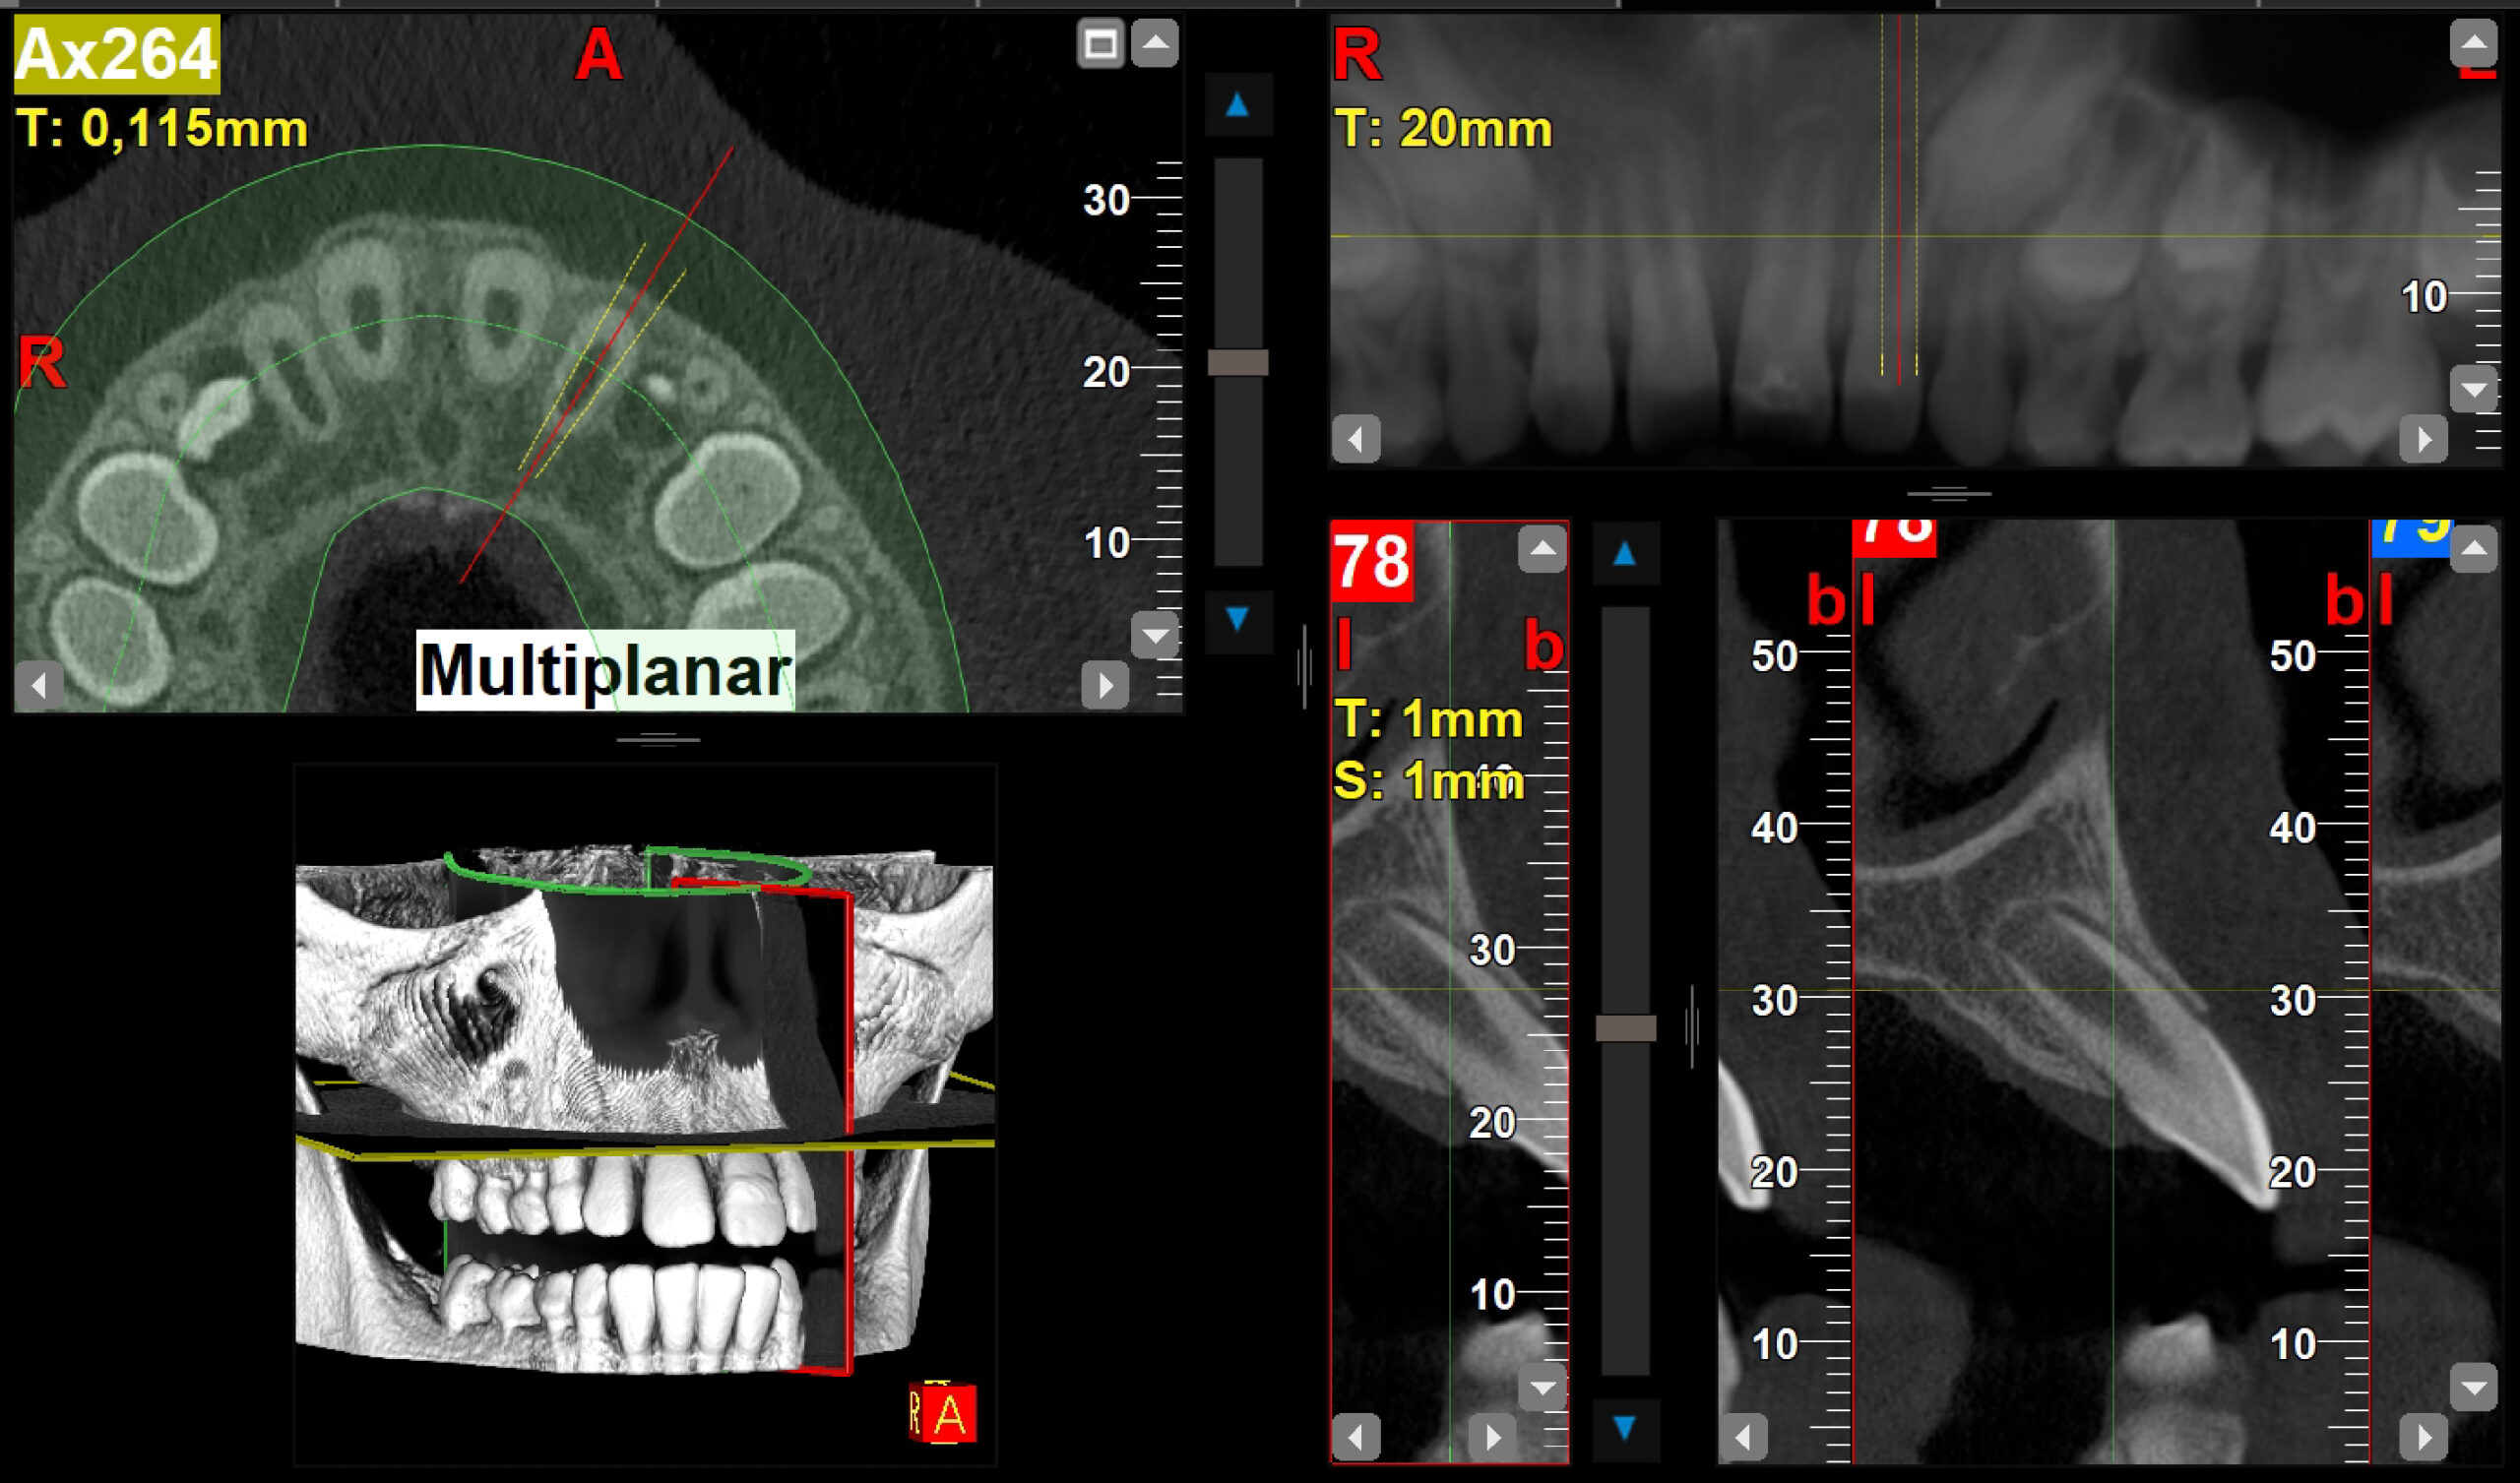

2.1 fractura coronal

Endodoncia y Traumatología Dental

Radiografías